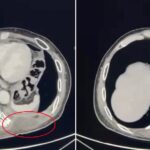

Si tratta di un uomo di 67 anni, residente nella provincia dell’Aquila, colpito da un voluminoso tumore polmonare sinistro che aveva infiltrato strutture ossee e muscolari della parete toracica fino a raggiungere la cute. Dopo un percorso di chemioterapia e immunoterapia neoadiuvante, effettuato per ridurre la massa e rendere possibile la chirurgia, il paziente è stato sottoposto a una complessa procedura operatoria. Il trattamento chirurgico ha previsto la rimozione del tumore mediante lobectomia polmonare inferiore sinistra, la demolizione della porzione di parete toracica infiltrata, con asportazione delle strutture coinvolte (coste, muscoli e cute), e la successiva ricostruzione parietale attraverso il posizionamento di una protesi biologica ADM (Acellular Dermal Matrix) nella sede priva delle costole. A completamento della riparazione è stato effettuato il trasferimento di un lembo muscolo-cutaneo destro, utilizzando il muscolo gran dorsale controlaterale, così da ricostituire l’integrità anatomica e funzionale della parete toracica.

A distanza di tre mesi dall’intervento, il paziente gode di buona salute ed è libero da malattia. La Tac post-operatoria evidenzia la piena integrazione della protesi con le strutture osteo-muscolari, confermando il completamento del processo di riparazione. La prestazione ad alta specializzazione ha permesso di eradicare del tutto il tumore e di ripristinare un’adeguata qualità di vita, con un risultato ottimale sotto il profilo funzionale ed estetico.